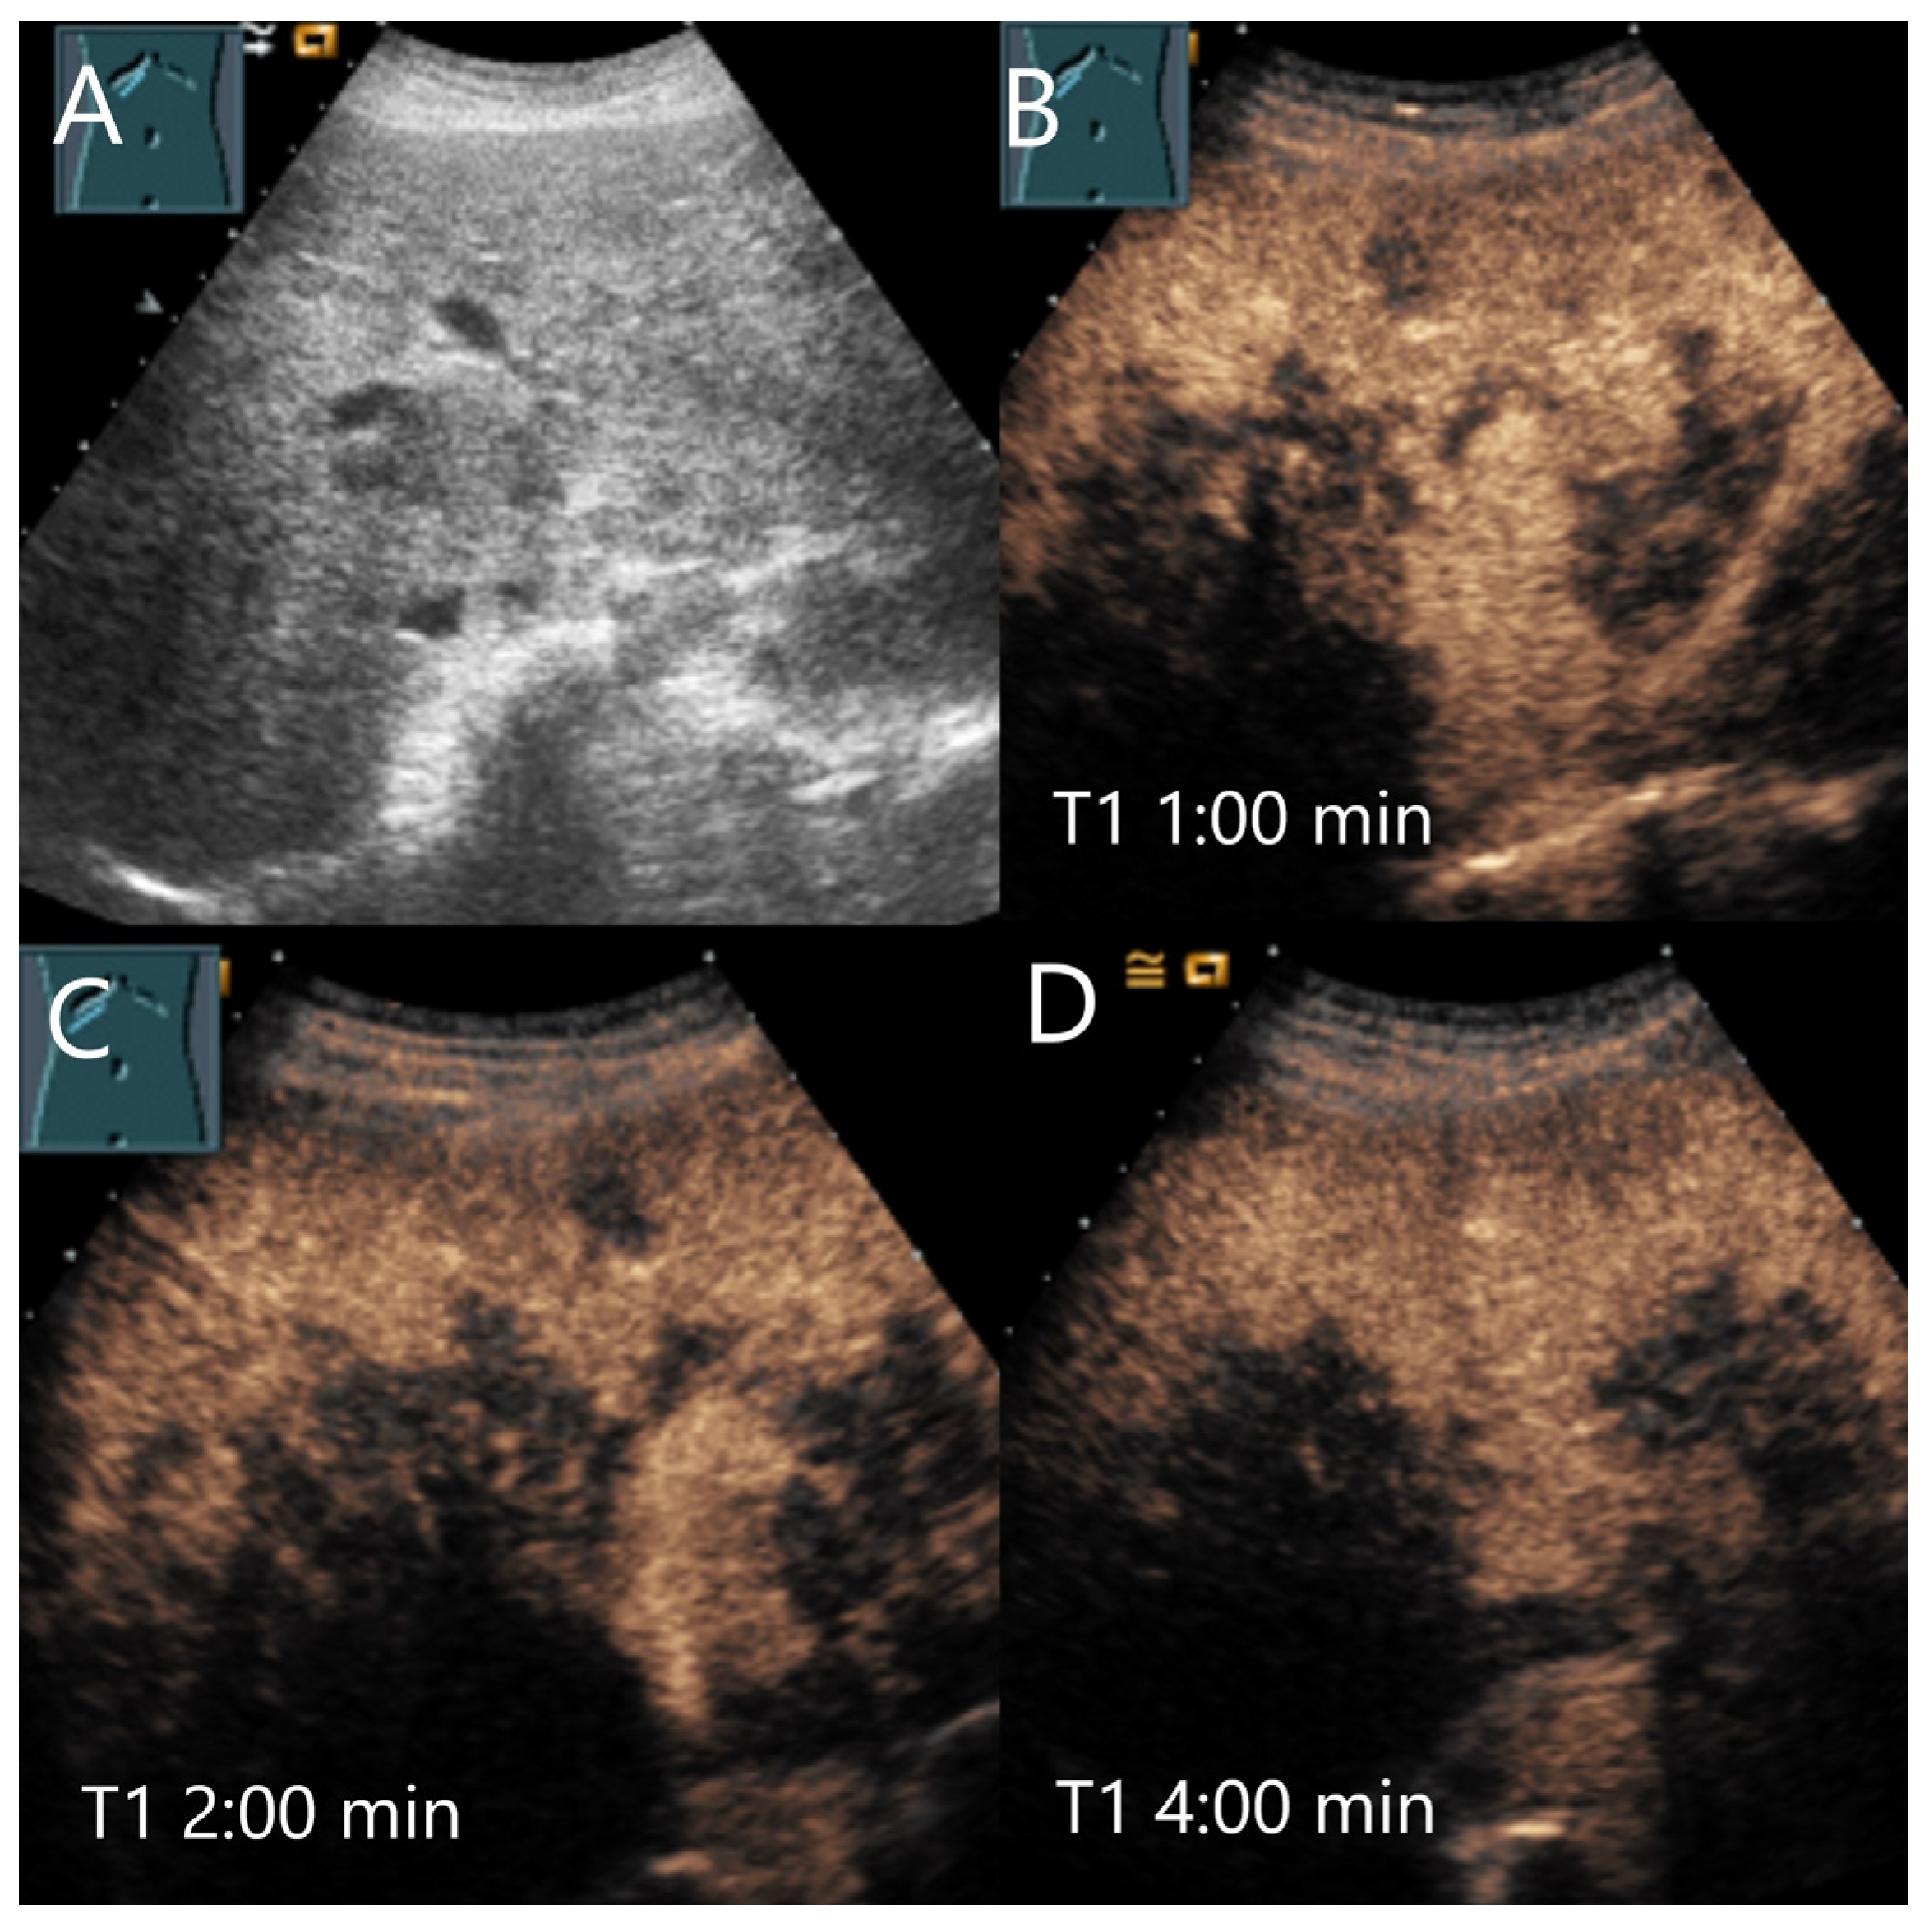

| HCA | Hypo-/iso-/hyperechoic HNF1a HCA (steatotic HCA) are frequently hyperechoic. | centripetal or mixed/diffuse filling. | Iso- or late slight hypoenhancement. Hyperenhancement in some I-HCA. | Absence of portal and central veins. |